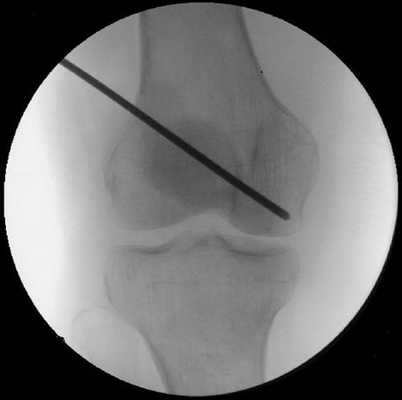

Внутренняя декомпрессия. Сутью такой операции является формирование в кости нескольких небольших, либо одного крупного канала с целью уменьшения так называемого внутрикостного давления. Такая технология обеспечивает образование новых сосудов, питающих пораженную суставную часть, устраняет костный коллапс, а также эффективным образом препятствует развитию остеоартроза.

Внутренняя декомпрессия на начальных этапах проявления остеонекроза